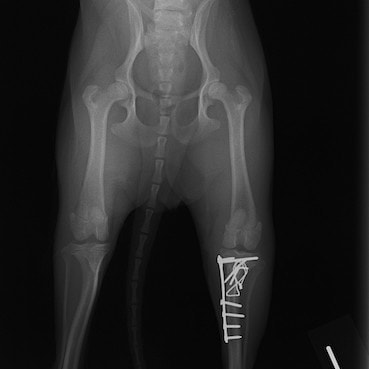

症例3:キルシュナーワイヤーのピンニングによる整復

ペルシャ猫 11ヶ月齢 雄

他院にて左大腿骨遠位の成長板骨折(salter-harrisⅠ型)が認められており、治療相談を目的として来院。当院にて、キルシュナーワイヤーを用いたピンニングにより骨折部位の整復を行いました。術後の経過は良好で、現在も経過観察中です。

術前レントゲン

術後レントゲン